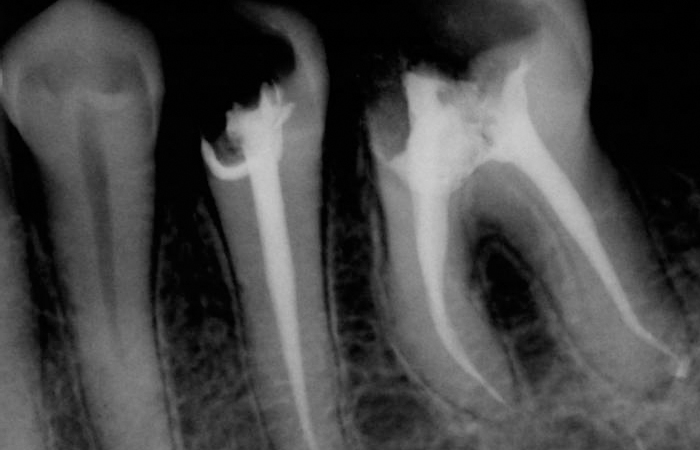

A root canal is a treatment used to repair and save a tooth that is badly decayed or becomes infected. During a root canal procedure, the nerve and pulp are removed and the inside of the tooth is cleaned and sealed. Without treatment, the tissue surrounding the tooth will become infected and abscesses may form.

“Root canal” is the term used to describe the natural cavity within the center of the tooth. The pulp or pulp chamber is the soft area within the root canal. The tooth’s nerve lies within the root canal.